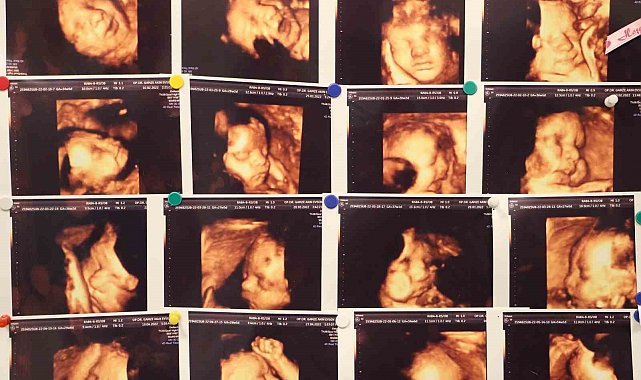

Memorial Hastanesi Kadın Hastalıkları ve Doğum Uzmanı Op. Dr. Gamze Akın Evsen, çocuk sahibi olmaya hazırlanan çiftlerin yaşadığı en büyük travmalardan biri olan gebelik kayıpları, çoğu anne adayının psikolojisinin bozulmasına ve çaresizlik hissine kapılmasına neden olduğunu belirterek, "Klinik olarak saptanan gebeliklerin yüzde 10-15'i düşükle sonuçlanmakla beraber bu durumun tekrar etmesi yani tekrarlayan gebelik kayıplarında oran Yüzde 3 ila 5'tir" dedi.

"Klinik olarak saptanan gebeliklerin yüzde 10-15'i düşükle sonuçlanmakla beraber bu durumun tekrar etmesi yani tekrarlayan gebelik kayıplarında oran Yüzde 3 ila 5'tir. Tekrarlayan gebelik kayıplarında en sık kromozomal sıkıntılar olmakla beraber, genetik anomaliler, hormonsal sıkıntılar, kan pıhtılaşması, rahmin yapısal bozuklukları, annede var olan diyabet ve guatr gibi sistemin hastalıklar, annede tekrarlayan enfeksiyonlar, bağışıklık sistemi sorunları ve çevresel faktörler görülebilmektedir."

Gebelik kayıplarının sebeplerinin değerlendirilmesi için çeşitli testlerin yapılması gerektiğini aktaran Dr. Evsen, "Özellikle tekrarlayan gebelik kayıplarının sebepleri değerlendirildiğinde öncelikle anne ve babanın kronik hastalıkları, tıbbi öyküleri, ailede mevcut genetik hastalıkları gibi durumların ayrıntılı bir şekilde sorgulanması gerekmektedir. Ayrıntılı bir fizik muayene sonrasında genetik sorunlar açısından genetik testi, pıhtılaşma bozukluğu açısından trombofili paneli incelenmesi, genel hastalıkların değerlendirilmesi için, akş, ogtt, hba1c, tsh, prl gibi testler istenebilmektedir. Yine bağışıklık sitemi değerlendirmesi için bazı testler istenmekle beraber rahmin yapısal sıkıntıları için hsg dediğimiz rahim filmi çekilmesi önerilmektedir. Tüm bunlar böyle kısaca özetlenebilse de bu süreç hasta için oldukça yıpratıcı kaygı verici olabilmektedir" dedi.